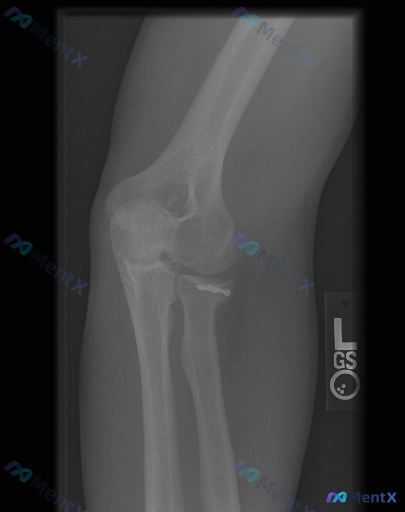

整理到一张左侧肘关节的侧位X光片,先放核心影像所见,大家来聊聊思路: - 标注L,左侧肘关节侧位 - 肱尺、肱桡关节对位基本可,无明显脱位/半脱位 - 关键:桡骨头颈部可见高密度金属内固定物(微型螺钉类) - 前/后脂肪垫征阴性,无明显“帆船征” - 整体骨密度无弥漫异常,关节面尚平整,无明显急性骨...

整理到一份左肘关节术后的复查影像资料,X光报告已经出了,但关于这份影像的“异常”解读可能存在不同角度。 核心信息先放出来: - 基础情况:左肘关节侧位片,标记L - 明确发现:肱骨小头/外髁区域有金属内固定物(高密度影,考虑克氏针或微型螺钉) - 骨骼整体:对位良好,关节关系正常,未见新的骨折线 -...